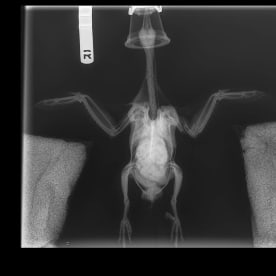

An x-ray of a kereru. Photo: Wildlife Hospital Dunedin.